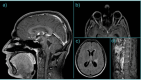

Case presentation: Here we present a case of hydrocephalus in neurosarcoidosis, complicated by generalized seizures, in a 29-year-old Caucasian male patient treated with medical treatment only, with optimal response.